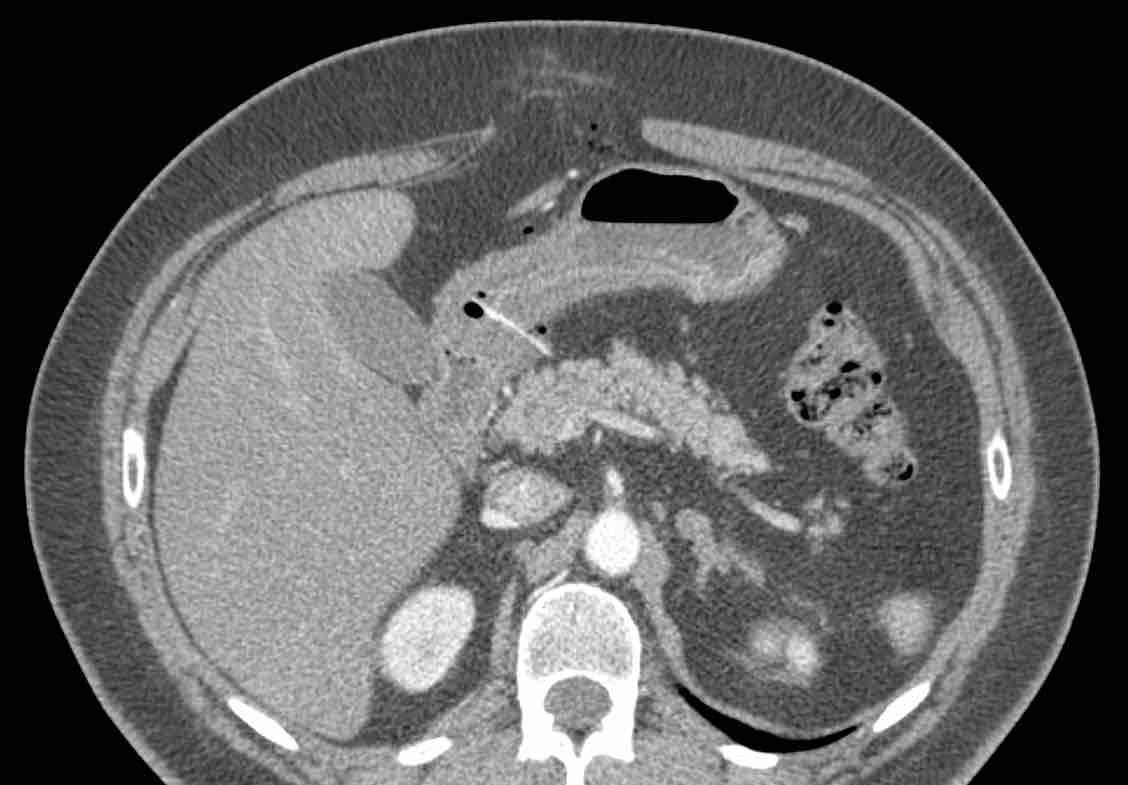

Khi được tìm kiếm có chủ đích, việc phát hiện các xương tăng tỷ trọng (mũi tên) trong lòng ruột không phải là hiếm gặp, như ở ba bệnh nhân không có triệu chứng này.

Các dị vật sắc nhọn có khả năng xuyên thủng thường gặp nhất là xương cá, xương gà và que gỗ như tăm xỉa răng hoặc tăm cocktail.

Không phải lúc nào cũng có thể phân biệt xương với que gỗ trên CT, nhưng xương cá thường tăng tỷ trọng rõ và có hình dạng cong, trong khi que gỗ ít tăng tỷ trọng hơn và có hình dạng thẳng hơn.